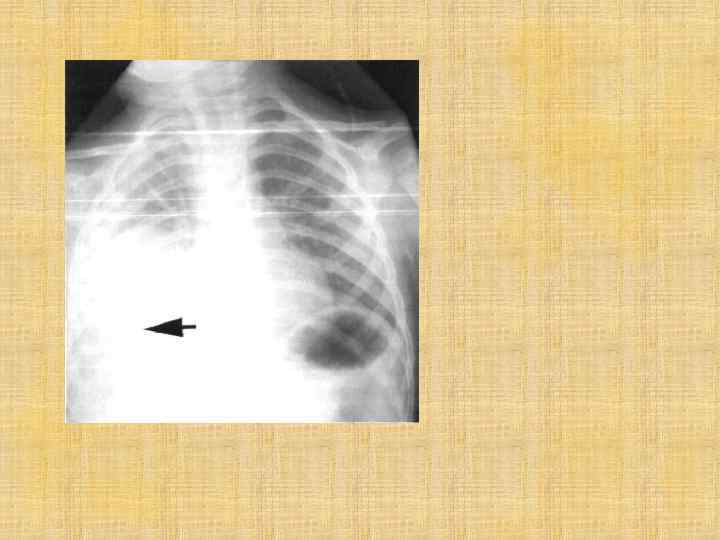

Хронический бронхиолит с облитерацией Заболевание, развивающееся вследствие острого облитерирующего бронхиолита, морфологическим субстратом которого является облитерация бронхиол и артериол одного или нескольких участков легких, приводящая к нарушению легочного кровотока и развитию эмфиземы Синдром одностороннего сверхпрозрачного легкого (синдром Мак Леода) представляет собой частный случай данного заболевания. Клинически проявляется одышкой и другими признаками дыхательной недостаточности разной степени выраженности, локальными физикальными данными в виде стойкой крепитации и мелкопузырчатых хрипов. У детей старшего возраста может сопровождаться бронхообструктивным синдромом, имеющим торпидное, плохо поддающееся лечению бронходилятаторами течение. При наличии клинических данных и рентгенологических признаков сверхпрозрачности сцинтиграфически определяется резкое снижение легочного кровотока в пораженных отделах легких.

Синдром Мак Леода